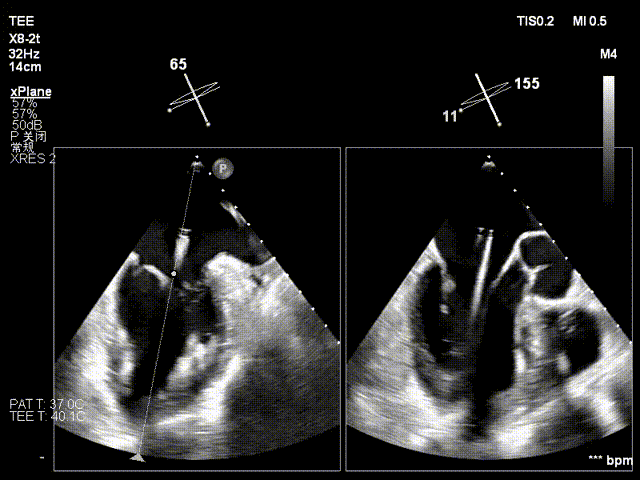

术中操作(关键步骤超声)

在全麻下,于心尖入路完成ValveClamp®装置植入。术中多学科团队密切配合,超声全程实时指导操作。最终,于2偏3区成功植入一枚Ⅲf夹子,一次夹合完成。前叶夹合量12mm,后叶夹合量10mm,反流降至1+,导管操作时间30分钟。术后平均跨瓣压差3mmHg。

术中剪影